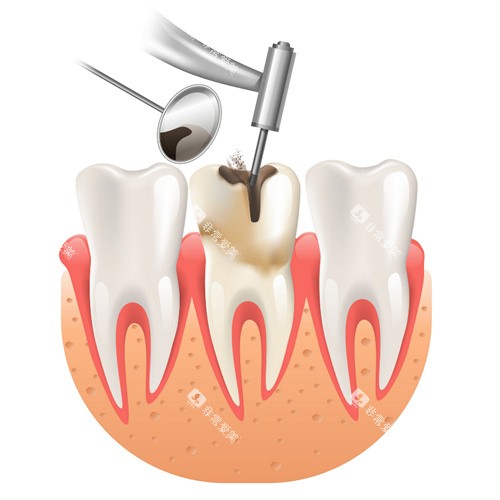

科尔口腔引进了一系列国内外可靠的牙科设备,如智能化口腔全景机、激光治疗仪等。

这些设备能够为医生提供更加更准的诊断信息,提高治疗的结果和效率。

例如,智能化口腔全景机能够快速、清晰地拍摄口腔全景图像,帮助医生超全了解患者的口腔状况。

可靠的技术和设备是确保治疗结果的重要因素。

选择牙科诊所时,要了解其是否采用了可靠的牙科技术和设备。

例如,智能化诊断技术、不痛治疗技术等。